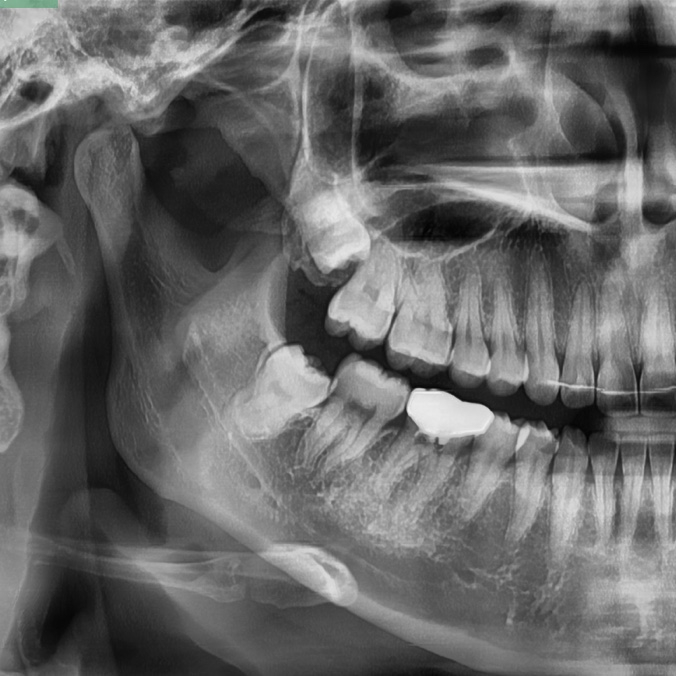

사랑니는 크게 일반 자연치아처럼 정상적으로 자리를 잡으며 나는 정상사랑니, 누운 형태로 자라 절반 정도만 잇몸을 뚫고 나온 반매복사랑니, 애초에 잇몸을 뚫고 나오지 못한 채 잇몸 안에서 자라는 매복사랑니 3가지 형태로 나눌 수 있습니다.

그 중에서도 사랑니는 반매복 사랑니인 경우가 많은데요. 반매복 사랑니는 완전한 매복사랑니보다 잇몸염증을 유발하거나 인접치아를 손상시키는기 더 쉽기 때문에 사랑니발치를 하는 것이 현명합니다.

반매복 또는 매복사랑니의 경우에는 단순히 발치만으로도 제거되기 보다는 잇몸 절개를 해야하는 등의 난도 높은 시술이 필요할 수 있기에 반드시 약수치과 전문의와의 충분한 상담을 통해 진행하셔야 하는데요.

또한 약수치과 바른영치과는 사랑니발치 시 느끼게 될 통증에 대한 두려움에 통증이 심함에도 불구하고 사랑니발치를 미루고 있는 환자분들을 위하여 3단계 마취시스템을 통해 통증에 대한 두려움을 줄여드리고 있으며, 환자의 사랑니 형태를 면밀히 관찰 후 치료를 도와드릴 수 있도록 3D-CT 등 정밀진단장비를 보유하고 있습니다.